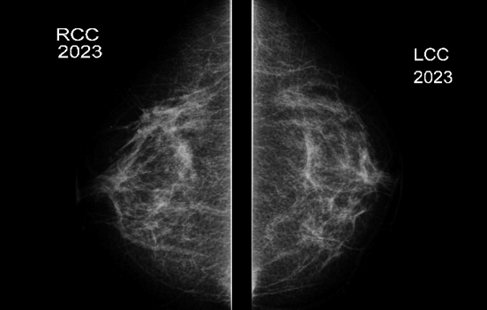

• En Mama DER CSE 10hr 5cmp se visualiza pérdida de la arquitectura del parénquima visualizándose imagen nodular hipoecogenica, irregular, no circunscrita, de contornos mal delimitados, y sombra posterior, con señal periférica al Doppler color, se correlaciona con distorsión visualizada en MX DER CC.

• En la mama derecha en el cuadrante superior externo hora 10 a 5cm de pezón y en correlación con asimetría mamográfica se observa un área nodular mal delimitada e hipoecogénica heterogénea que mide 13 x 15mm

• Área nodular mal delimitada en la mama derecha que se correlaciona con imagen mamográfica y que requiere estudio histológico con Biopsia Core bajo Ultrasonido.

• BIRADS 4C.-